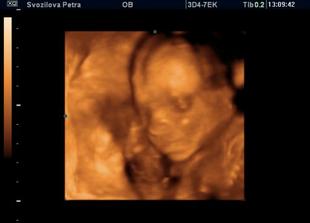

Nase miminko